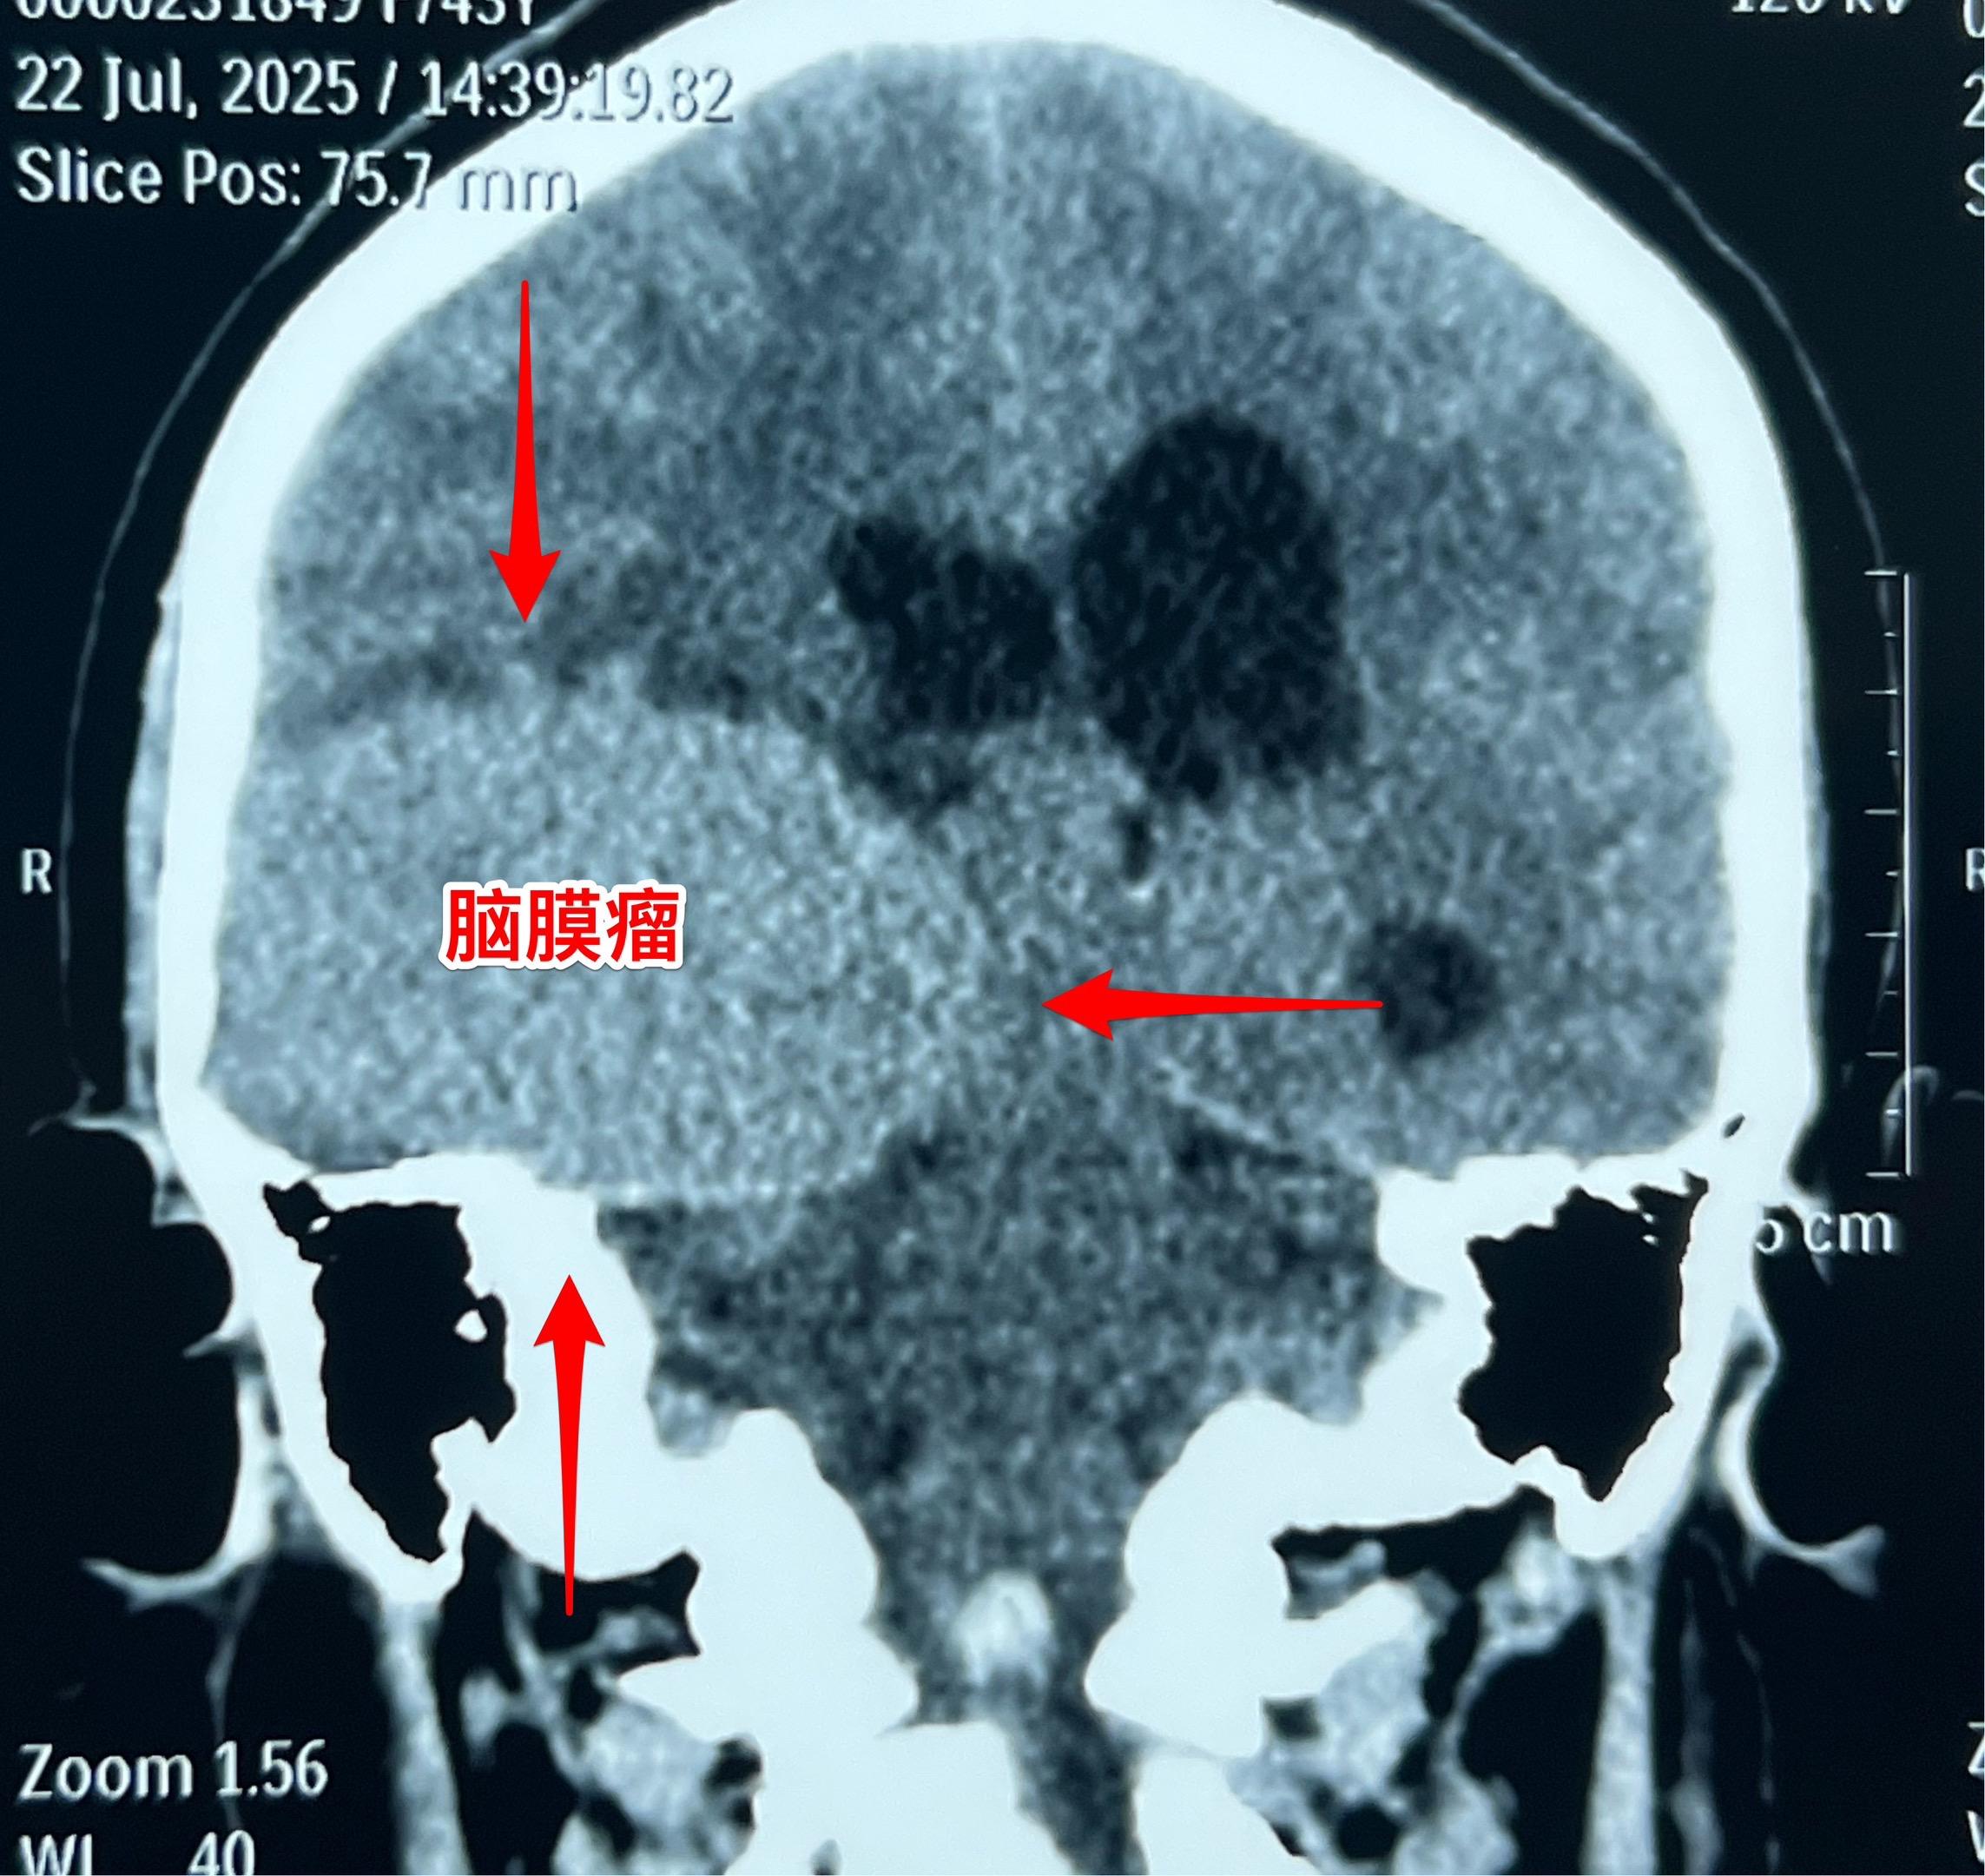

藏族牧民脑肿瘤被发现时像鸡蛋一样大。青海省黄南州藏族牧民,43岁,女性,平时以放养牦牛为生,家里有一百多头牦牛,她夫妻二人完全不能说汉语。 她头痛五年了,视力下降一年,迟迟没有就医,今年七月份因视力很差了才到西医医院检查,发现病根儿是脑膜瘤。如图所示,脑膜瘤像鸡蛋一样大。 发现脑肿瘤后,他们第一步是找活佛预判凶吉,指导治疗方向! 2025年8月1日作了手术,将肿瘤完全切除。希望她能顺利出院!